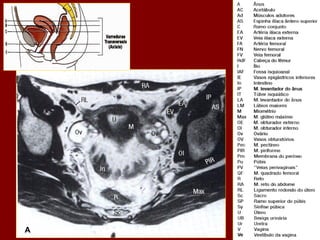

Ac Colo ascendente AP Nível de ar fluido do estômago Ao Aorta Az Veia ázigo CA Tronco celíaco cc Cartilagem costa! CD Dueto cístico CHA Artéria hepática comum CHD Dueto comum CL Lobo caudado fígado D Diafragma DBM Músculos profundos do De Colo descendente D2 Parte descendente do duodeno D3 Parte horizontal do duodeno E Esôfago FL Ligamento falciforme GB Vesícula biliar HA Artéria hepática Hz Veia IMV Divisão da veia mesentérica inf. A IVC Veia cava inferior LC Ramo esq. do diafragma LG Glândula supra-renal esq. LHV Veia hepática esquerda LIL Lobo inf. Esq. do pulmão LRV Veia renal esquerda LK Rim esquerdo LU Ureter esquerdo LL Lobo esquerdo do fígado MHV Veia hepática média P Pâncreas PA Antro pilórico do estômago

Ac Colo ascendente AP Nível de ar fluido do estômago Ao Aorta Az Veia ázigo CA Tronco celíaco cc Cartilagem costa! CD Dueto cístico CHA Artéria hepática comum CHD Dueto comum CL Lobo caudado fígado D Diafragma DBM Músculos profundos do De Colo descendente D2 Parte descendente do duodeno D3 Parte horizontal do duodeno E Esôfago FL Ligamento falciforme GB Vesícula biliar HA Artéria hepática Hz Veia IMV Divisão da veia mesentérica inf. IVC Veia cava inferior B LC Ramo esq. do diafragma LG Glândula supra-renal esq. LHV Veia hepática esquerda LIL Lobo inf. Esq. do pulmão LRV Veia renal esquerda LK Rim esquerdo LU Ureter esquerdo LL Lobo esquerdo do fígado MHV Veia hepática média P Pâncreas PA Antro pilórico do estômago

Ac Colo ascendente AP Nível de ar fluido do estômago Ao Aorta Az Veia ázigo CA Tronco celíaco cc Cartilagem costa! CD Ducto cístico CHA Artéria hepática comum CHD Ducto comum CL Lobo caudado fígado D Diafragma DBM Músculos para vertebrais De Colo descendente D2 Parte descendente do duodeno D3 Parte horizontal do duodeno E Esôfago FL Ligamento falciforme GB Vesícula biliar HA Artéria hepática Hz Veia IMV Divisão da veia mesentérica inf. C IVC Veia cava inferior LC Ramo esq. do diafragma LG Glândula supra-renal esq. LHV Veia hepática esquerda LIL Lobo inf. Esq. do pulmão LRV Veia renal esquerda LK Rim esquerdo LU Ureter esquerdo LL Lobo esquerdo do fígado MHV Veia hepática média P Pâncreas PA Antro pilórico do estômago

Ac Colo ascendente AP Nível de ar fluido do estômago Ao Aorta Az Veia ázigo CA Tronco celíaco cc Cartilagem costa! CD Dueto cístico CHA Artéria hepática comum CHD Dueto comum CL Lobo caudado fígado D Diafragma DBM Músculos profundos do De Colo descendente D2 Parte descendente do duodeno D3 Parte horizontal do duodeno E Esôfago FL Ligamento falciforme GB Vesícula biliar HA Artéria hepática Hz Veia IMV Divisão da veia mesentérica inf. D IVC Veia cava inferior LC Ramo esq. do diafragma LG Glândula supra-renal esq. LHV Veia hepática esquerda LIL Lobo inf. Esq. do pulmão LRV Veia renal esquerda LK Rim esquerdo LU Ureter esquerdo LL Lobo esquerdo do fígado MHV Veia hepática média P Pâncreas PA Antro pilórico do estômago